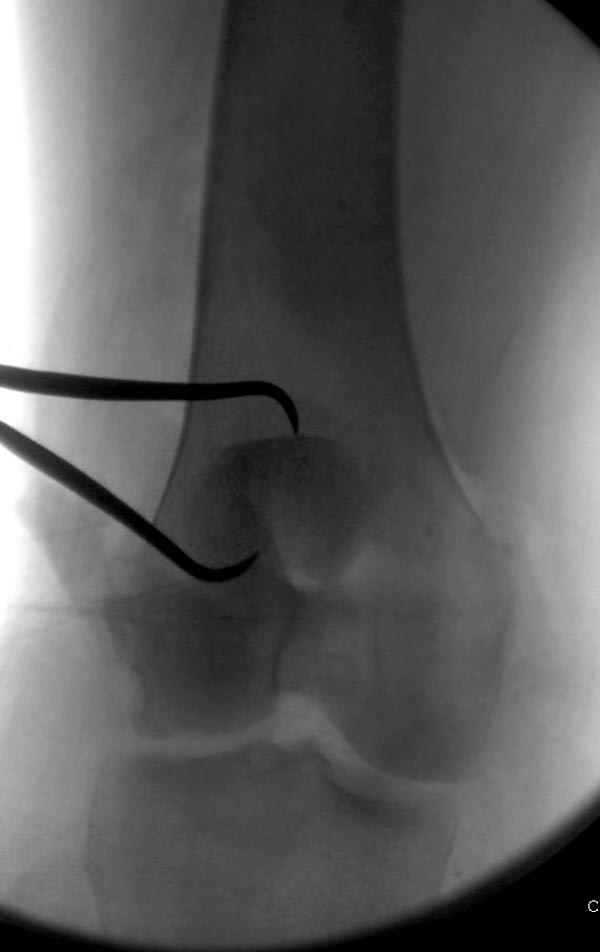

На операции: Irrigation&Debridment около 10 литров раствора, по два стержня в сегменте, фиксация диагонального, с дефектом, перелома надколенника тремя cannulated 4мм шурупами, ушивание поперечного разрыва связки 5.0 Ethibon sutures, разрыв находился на 2 см ниже надколенника (срез чем-то острым), повторная ирригация раны, взятие посева на аэробическую и анэробическую культуру, окончательная фиксация стержней наружного фиксатора 50см Carbon Fiber Bars, вакуумное закрытие. Мониторинг показал, что компартмент синдрома нет.

Сегодня досылаю остальные снимки, которые не прошли вчера. Как вчера писал, после фиксации перелома надколенника с дефектом кости и собственной связки, наложили ваккуум и наружный фиксатор. (снимки 4-9)

Внешний фиксатор держим около 6 недель, поэтому был выбран метод фиксации шурупами и еще линия перелома была диагональной, не было нужды в tension band technique, cannulated screws удобнее, провел спицы и по ним шурупы.

Почти все компании имеют стержни 3-4-5 мм в диаметре для наружного фиксатора и только одна 6 мм с hydroxyapatite покрытием. Стержни имеют различную заточку и self drilling, что связано с патентной проблемой каждой компании, Стержень проводим по двойному проводнику, после предварительного сверления меньшим диаметром сверла, 3.8мм при 5мм, стержень в диафизе предпочтительно провести вручную, за исключением метафиза, где используется дрель.

На слайдах (не четко обозначены бедро и голень): на бедре по наружно-передней поверхности, между вастус латералис и прямой головками, а на голени по передне-медиальной поверхности, желателен подбор длины резьбовой части стержня по ширине поперечника кости. На снимке: дистальное кольцо, метод проведения стержня через канюлю-проводник.